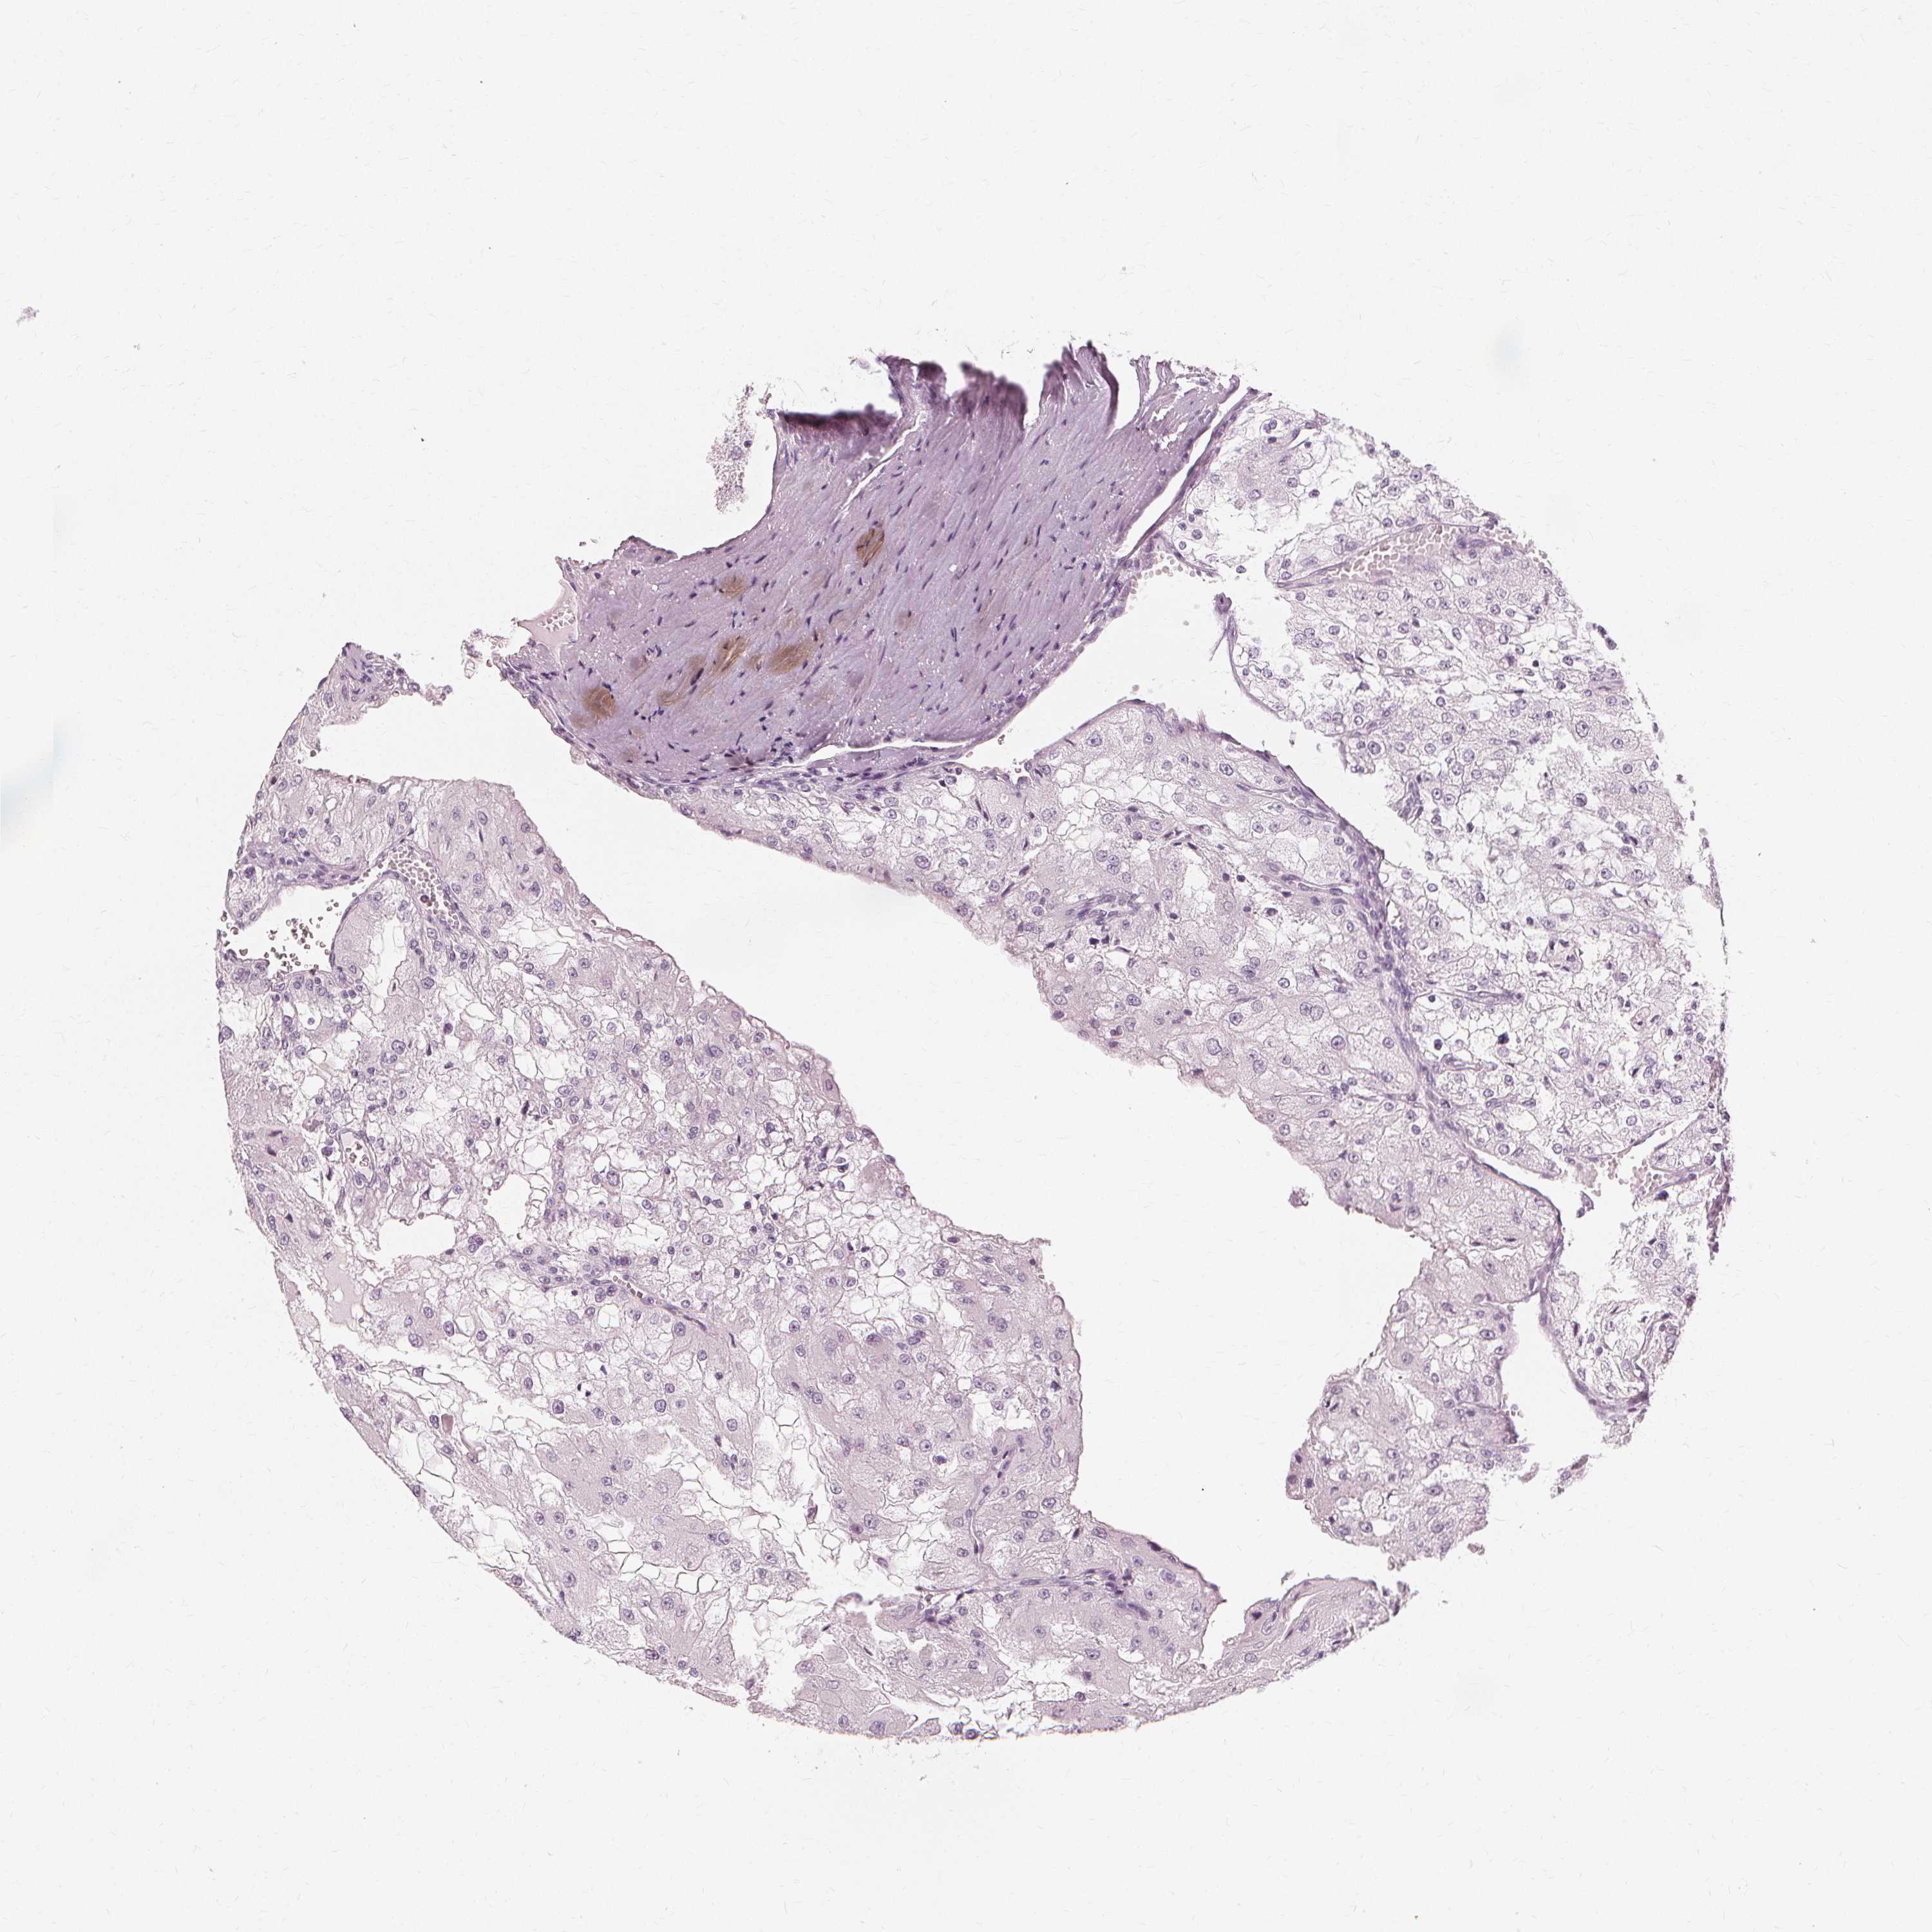

KIDNEY RENAL CLEAR CELL CARCINOMA (VALIDATION) - Interactive survival scatter ploti

The Survival Scatter plot shows the clinical status (i.e. dead or alive) for all individuals in the patient cohort, based on the same data that underlies the corresponding Kaplan-Meier plots. Patients that are alive at last time for follow-up are shown in blue and patients who have died during the study are shown in red.

The x-axis shows the expression levels (FPKM) of the investigated gene in the tumor tissue at the time of diagnosis. The y-axis shows the follow-up time after diagnosis (years). Both axes are complimented with kernel density curves demonstrating the data density over the axes. The top density plot shows the expression levels (FPKM) distribution among dead (red) and alive patients (blue). The right density plot shows the data density of the survived years of dead patients with high and low expression levels respectively, stratified using the cutoff indicated by the vertical dashed line through the Survival Scatter plot. This cutoff is automatically defined based on the FPKM cutoff that minimizes the p-score. The cutoff can be changed by dragging the vertical line or by entering a cutoff value in the square labeled "Current cut-off".

Under the Survival Scatter plot the p-score landscape (black curve; left axis) is shown together with dead median separation (red curve; right axis). Dead median separation is the difference in median mRNA expression between patients who have died with high and low expression, respectively. It is calculated as follows: median FPKM expression of dead patients with high expression - median FPKM expression of dead patients with low expression. This is intended to aid the user in visually exploring custom cutoffs and the associated p-scores and dead median separation.

Individual patient data is displayed and can be filtered by clicking on one or more of the category buttons on the top of the page. Categories describing expression level and patient information include: high, low, alive, dead, female, male and tumor stages. The scale of the x-axis can be toggled between linear and log-scale by clicking on the "x log" button. Mouse-over function shows TCGA ID, patient information and mRNA expression (FPKM) for each patient.

& Survival analysisi

Kaplan-Meier plots summarize results from analysis of correlation between mRNA expression level and patient survival. Patients were divided based on level of expression into one of the two groups "low" (under cut off) or "high" (over cut off). X-axis shows time for survival (years) and y-axis shows the probability of survival, where 1.0 corresponds to 100 percent.

NXPE1 is not prognostic in Kidney Renal Clear Cell Carcinoma (validation)

TCGA RNA samplesi

RNA-seq data is reported as average FPKM (number Fragments Per Kilobase of exon per Million reads), generated by the The Cancer Genome Atlas (TCGA) .

Normal distribution across the dataset is visualized with box plots, shown as median and 25th and 75th percentiles. Points are displayed as outliers if they are above or below 1.5 times the interquartile range. FPKM values of the individual samples are presented next to the box plot.

Average pTPM 0.0

Number of samples 100